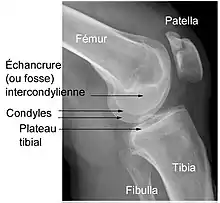

Éléments d'anatomie du genou

Le genou naturel est composé de trois parties osseuses :

- l’extrémité inférieure du fémur qui a la forme de deux roues accolées : les condyles ;

- l’extrémité supérieure du tibia, encore appelé plateau tibial ;

- la patella (ou rotule) : petit bouclier situé sur l’avant du fémur.